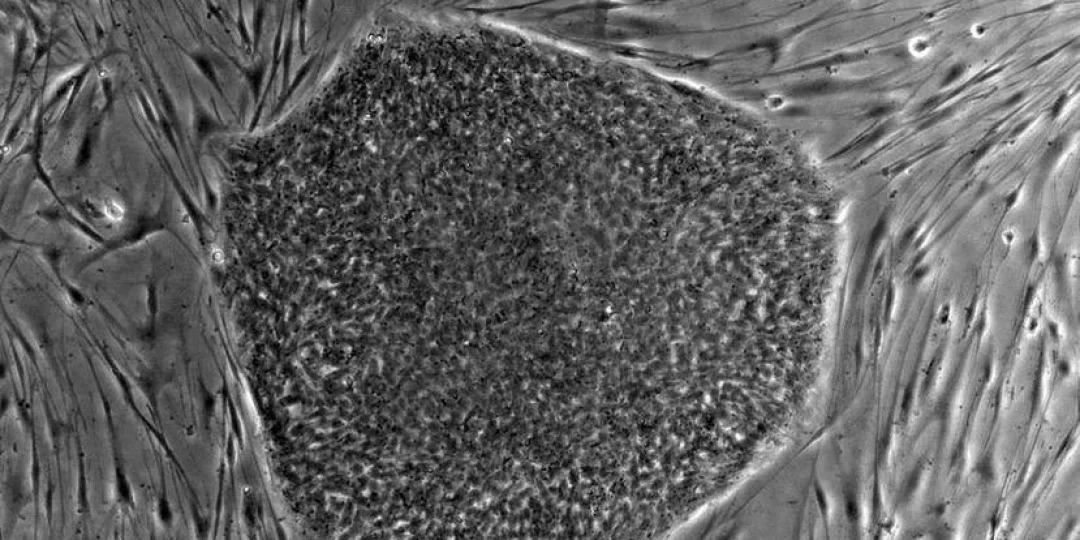

Los científicos nipones generaron ovogonia humana artificial, se trata del precursor del óvulo, dentro de los ovarios de una rata de laboratorio y sólo utilizando células madre humanas. Según explicaron, los resultados esta investigación y publicados en la revista Science, pueden ayudar a ganar la batalla contra la infertilidad.

Sin embargo, a raíz de los últimos avances hechos por el equipo científico que lidera Mitinori Saitou de la Universidad de Kyoto, se ha logrado el inédito hecho de crear un precursor de un óvulo usando células madre humanas implantadas en una estrecha aproximación al ovario de un ratón. https://www.ciudadanodiario.com.ar/nota/2018-9-22-10-37-7-horoscopo-hoy-los-tres-signos-del-zodiaco-que-comienzan-la-primavera-con-problemas

Según los científicos de la Universidad de Kyoto (Japón), el trabajo comenzó mediante el uso de comprobadas técnicas con las cuales se convertía células sanguíneas humanas en células madre pluripotentes. Después, generaron una similitud con el ovario de un ratón usando células embrionarias. Luego colocaron células madre en los ovarios artificiales del ratón y allí las incubaron durante varios meses.

Luego de un tiempo, las células madre terminaron siendo un material con características específicas de los ovocitos en diferentes etapas de crecimiento: precursores de los óvulos humanos.